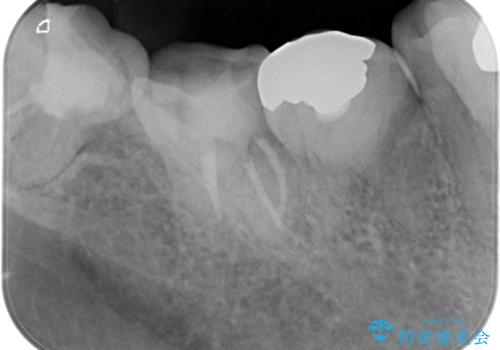

【根管治療】噛んだ時にしみる。最近になってズキズキ痛み、長引く痛みがある

- 噛んだ時にしみる。最近になってズキズキ痛み、長引く痛みがある。とのことで来院されました。

検査結果にて不可逆性歯髄炎の診断を行いました。

顕微鏡にて虫歯を取り除くと、深いクラックラインを認めることができ、クラックラインを全て除去し抜髄処置を行いました。